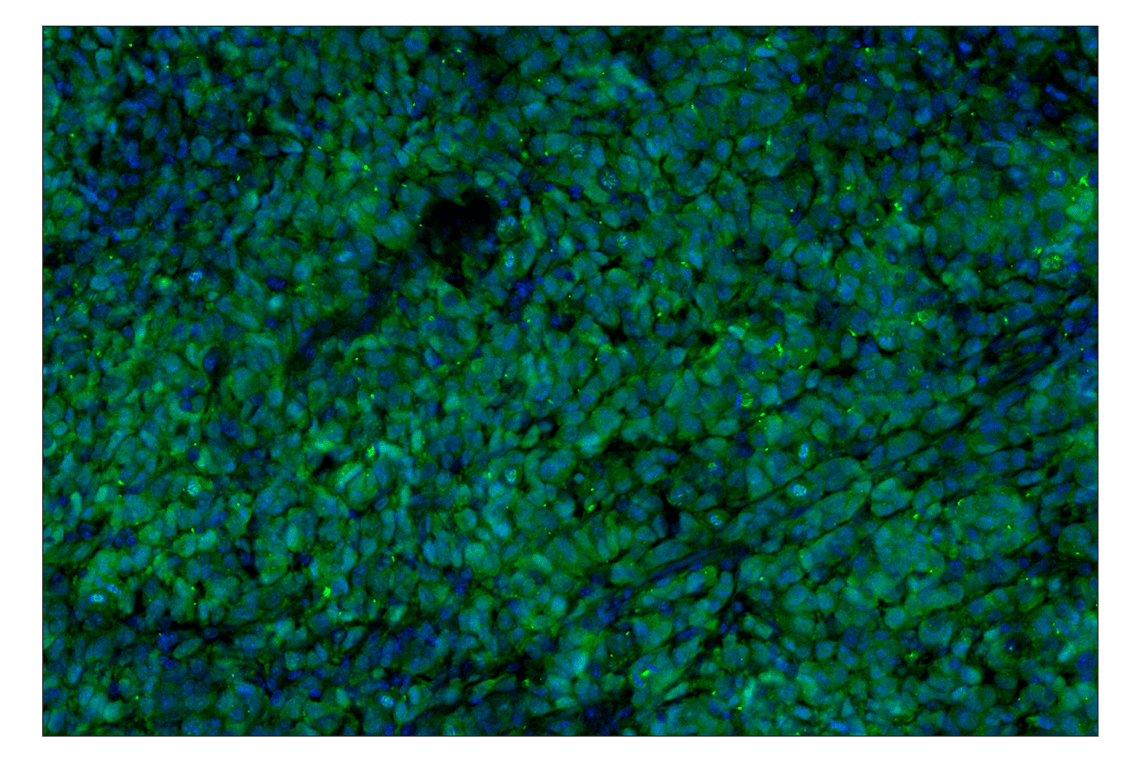

p16 INK4A (F2T7H) Rabbit Monoclonal Antibody (Alexa Fluor® 488 Conjugate) #38083

Immunohistochemistry (Paraffin) 1:50 - 1:200

p16 INK4A (F2T7H) Rabbit Monoclonal Antibody (Alexa Fluor® 488 Conjugate) recognizes endogenous levels of total p16 INK4A protein. This antibody does not cross-react with p15 INK4B protein. Non-specific cytoplasmic staining was observed in mouse small intestine epithelium by immunohistochemistry.